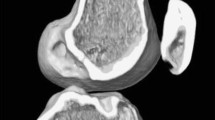

A total of 40 patients who underwent primary DB-ACLR with the TP technique using a curved guide were evaluated retrospectively. The tunnel axis angle in three orthogonal planes were evaluated on a three-dimensional surface model constructed using an axial computed tomography scan obtained after reconstruction. Then, correlations with tunnel length were analyzed.

Measurement of tunnel axis angle using three-dimensional computed tomography

Computed tomography (CT) scans were performed on all knees after ACL reconstruction. The knee was placed in full extension. Digital Imaging and Communications in Medicine data were extracted from the picture archiving and communication system. Data were segmented by Mimics software (Materialise, Leuven, Belgium), a commercially available image processing software used to create three-dimensional (3D) surface models from stacks of two-dimensional image data. The data were then imported into Geomagic Studio software, version 12.0 (Geomagic, Rock Hill, SC, USA), and the 3D surface model was projected into coronal, axial, and sagittal planes to measure the tunnel axis angle in each plane (Fig. 3). As described by Basdekis et al. [20], the angle between the tunnel and the line tangent to the distal and posterior aspects of the femoral condyles was measured in the coronal and axial planes. The sagittal plane angle between the tunnel and the extended intersectional line of the femoral shaft was measured. A lower tunnel angle in the sagittal plane indicated that the tunnel orientation is extended compared with the femoral shaft, while a higher tunnel angle in the sagittal plane indicated that tunnel orientation is flexed compared with the femoral shaft.

To measure the femoral tunnel length, the plane in which the entire length of the femoral tunnel showed the maximal width was selected. The distance between the centers of the intra-articular and extra-articular tunnel apertures was measured [21]. To evaluate its correlation with distal femoral anatomy, the lateral posterior condyle (LPC) AP size (LPC offset distance) and medial-to lateral (M-L) epicondylar distance were measured [21]. The incidence of posterior cortical damage was evaluated by 3D CT scan. Cases with posterior cortical damage or in which the tunnel center was not placed within the anatomical footprint boundary would have been excluded, but none occurred in this study.